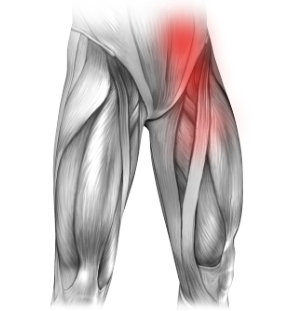

Zapalenie kaletki lewego mięśnia biodrowo lędźwiowego

Mięsień biodrowo lędźwiowy lewy jest w większości położony w jamie brzusznej i miednicy, a jego koniec przyczepia się do kości udowej w jej górnej części. Nadmierne przeciążenie może doprowadzić do zapalenia kaletki, co powoduje ból w lewej pachwinie promieniujący na nogę. Dolegliwości mogą być też odczuwane w biodrze i pośladku. Ból nasila się przy podnoszeniu z siedzenia (zwłaszcza rano) oraz podczas chodzenia. Najczęściej dolegliwości nasilają się nad ranem.

Obok badania lekarskiego, do postawienia diagnozy używa się często USG.

Leczenie może polegać na odpoczynku, przyjmowaniu leków przeciwzapalnych oraz fizjoterapii. Cięższe przypadki leczy się usuwając zapalny płyn poprzez wkłucie igły oraz podanie miejscowo leków wygaszających zapalenie. Jedynie w najcięższych przypadkach stosuje się leczenie chirurgiczne.